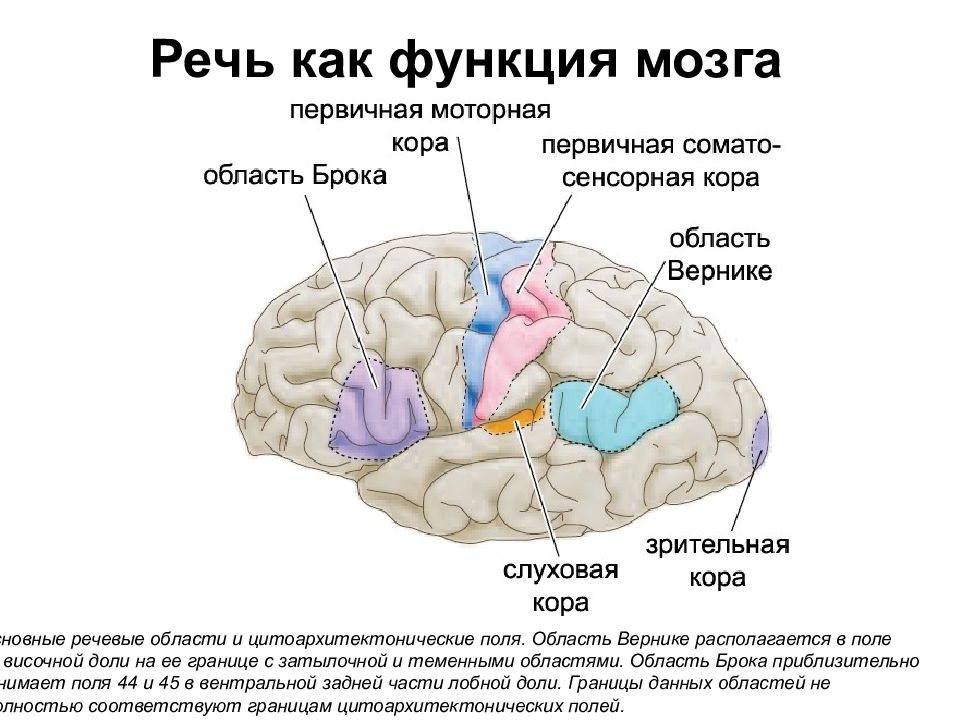

Схема чувствительных зон новой коры мозга